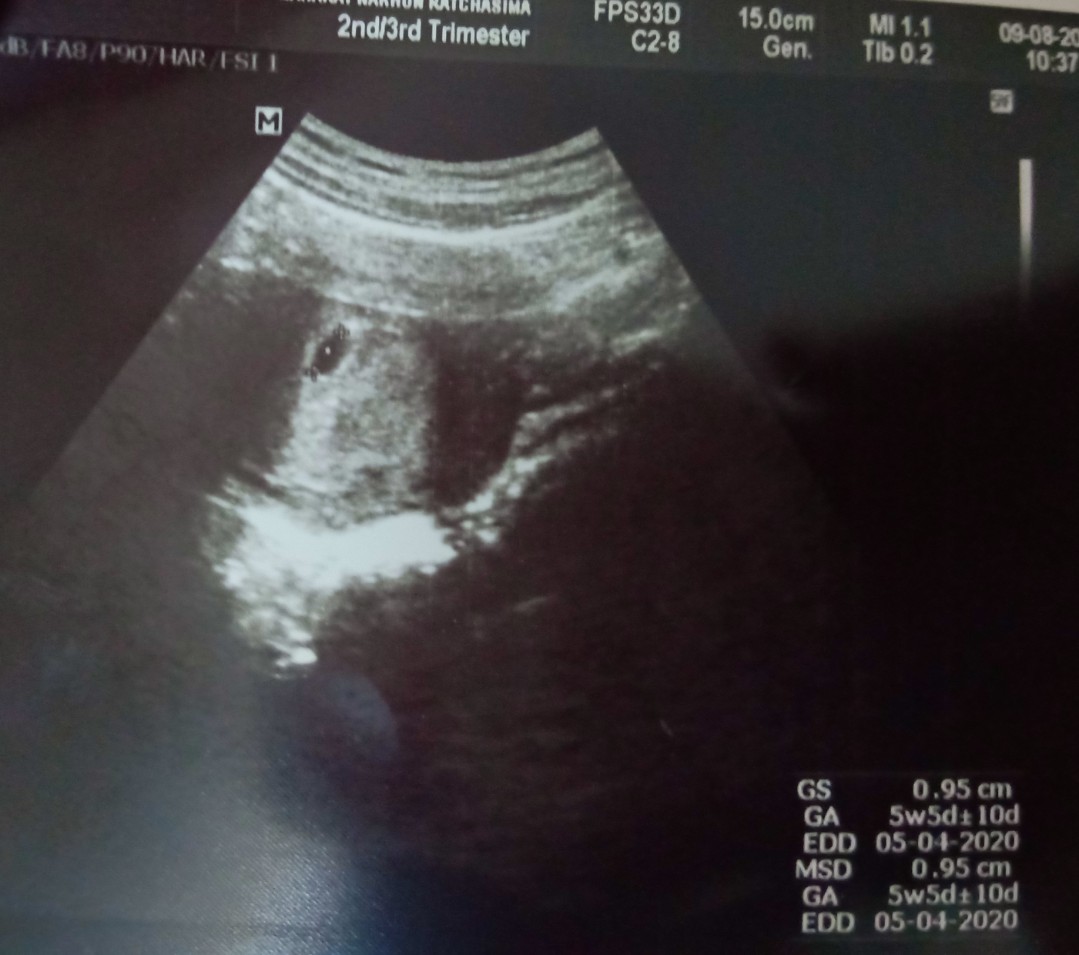

ตอนไปฝากท้องครั้งแรกอายุครรภ์ได้6 สัปดาห์ หมอนัดอีก1 เดือนได้10 สัปดาห์ ยังคลำไม่พบฟังไม่ได้ยิน หมอเลยอัลตราซาว ได้มาแบบนี้ค่ะ

เราซาวด์ตอน6วีค เห็นเปนจุดๆเล็กๆเองค่ะไม่ชัดด้วย พอ10วีคซาวด์อีกรอบเห็นเปนตัวดิ้นดุ๊กดิ๊กเห็นหัวใจกระพริบเลยค่ะ

ไปซาวด์มาตอน 6 สัปดาห์ครั้งแรก หมอบอกตัวเท่าเม็ดข้าวเหนียว ยาว 0.7 มิล ได้ยินเสียงหัวใจเต้นด้วยค่ะ ดีใจมากๆ

แม่บ้านนี้ 4 วีค ไม่เจออะไรเลยค่ะ ในภาพ 6วีค เจอถุงเล็กๆ ประมาณ 5 มิลค่ะ หมอนัดอีกที วันที่ 24 เมษายนนี้ค่ะ

อันนี้ของเราตอน 6w ค่ะ น้องยังตัวเล็กมากเลยยังไม่เห็น นัดไปอีกทีตอน 8w เห็นชัดแล้วค่ะ

ของเรา 6 สัปดาห์ประมาณนี้จ้า แม่อย่าเพิ่งเครียดไปน้าา